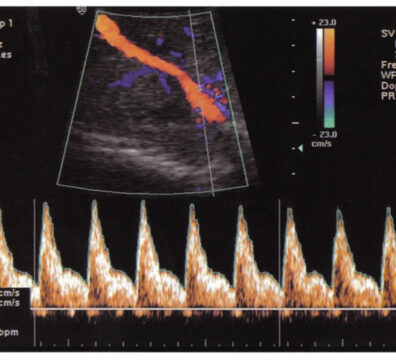

🌸 Doppler de arterias uterinas

El Doppler de arterias uterinas es una ecografía especial que evalúa cómo está fluyendo la sangre desde la mamá hacia la placenta.

Es una ecografía que utiliza la tecnología Doppler, la cual permite medir la velocidad y resistencia del flujo sanguíneo.

En este caso, se estudian las arterias uterinas, que son los vasos encargados de llevar sangre al útero y a la placenta.